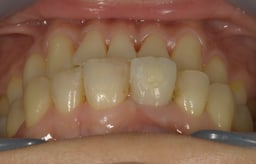

Simplified Microscopic Implant surgical Lifelike Esthetics を略した手術名で、米国カルフォルニア州サンタバーバラで歯周病専門医として開業されていた、 Dr. Dennis Shanelec(故人)が考案した治療法です。抜歯した直後に仮歯を入れることによって,歯を取り巻く骨(硬組織)や歯肉(軟組織)の状態を維持できる非常に優れた方法です。しかし、手術としての難易度は非常に高いレベルに位置づけられます。

抜歯した直後にインプラントを埋入し、仮の歯を作製、唇側の骨のボリュームを保つために人工骨と結合組織を同時に移植する非常に優れた方法です。